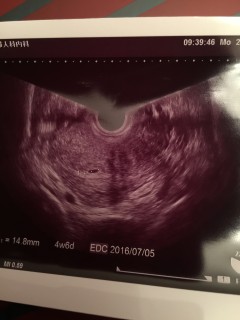

検査薬陽性が出て前回生理から6w4dのときに初診に行ってきました。 1年4ヶ月かかり諦めて気にしないようにしていた矢先の妊娠で嬉しかったです! 先生にも赤ちゃんくっきり見えるかもね~と言われたのですが、 あ~6週ではないけど、、 と。 5週だね!二週間後に来てと言われました。正常妊娠だし、胎嚢確認(4.8mmとちいさいですが…)できたのは嬉しいですがちゃんと育ってくれるか不安です。 二週間後に元気な姿見せてくれますよーに。